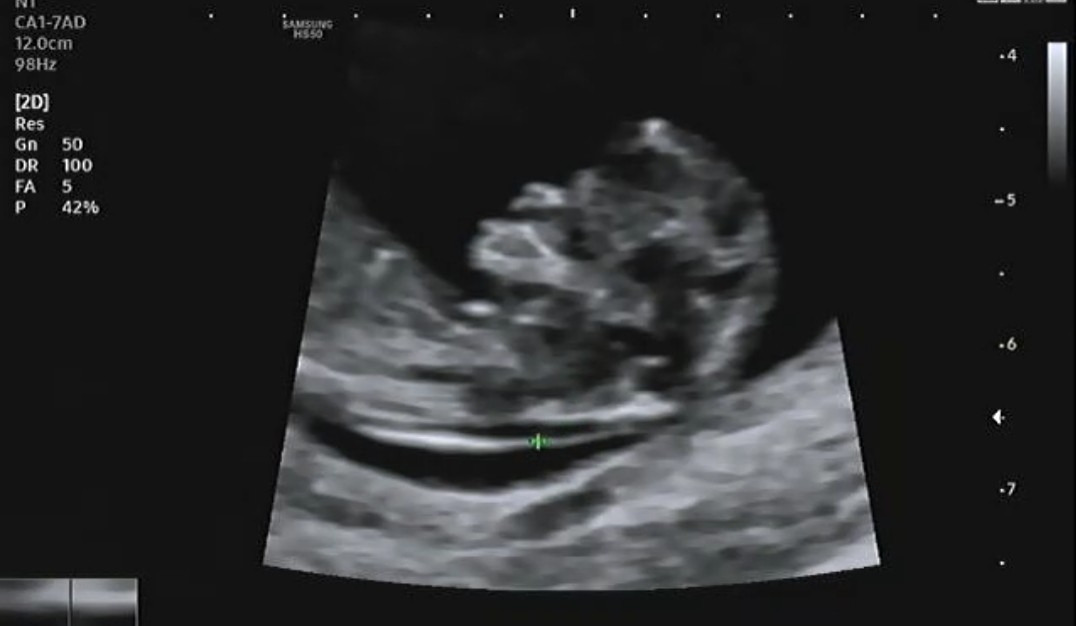

초음파를 확인하고 나면 기형아 검사를 위해 혈액검사를 시행한다. 기형아 검사는 총 2회로 진행되며 혈액검사와 태아 목 투명대를 측정하여 기형아 위험도를 검사한다. 1차 기형아 검사는 일반적으로 10~14주 사이에 많이 진행된다. 2차례 모두 진행이 끝나면 결과를 확인할 수 있는데 수치가 이상이 있다면 양수검사까지 진행을 하게 된다. 2회로 진행되는 기형아 검사는 100%의 정확도가 아닌 80~85% 정확도를 가지고 있으며 1차에서 이상소견이 발견되더라도 2차에는 정상 소견을 받는 사람도 많이 있다고 한다.

태아 목 투명대를 측정하여 다운증후군을 미리 예측할 수 있는데 다행히 나는 정상 수치라서 다음 초음파와 혈액검사 상 모두 정상이라면 크게 걱정할 필요가 없다는 이야기를 들었다. 목 투명대는 주수마다 정상 길이 범위가 다르며 보통 3mm 이상은 혈액검사뿐 아니라 양수검사를 시행한다.